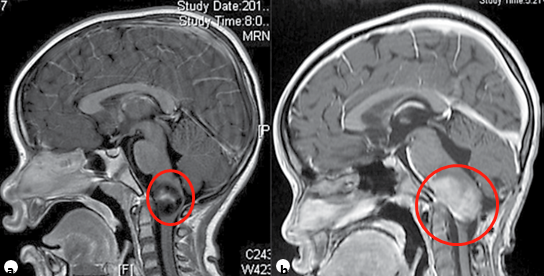

一个7岁的孩子,被检查出浸润性延髓-颈髓肿瘤,经过活检和组织病理学诊断,最终认定为低级别肿瘤。不愿让孩子受开颅之苦的父母最终选择了化疗、靶向等辅助治疗来控制肿瘤生长,但不幸的是,孩子的肿瘤仍在不断生长,威胁着孩子的生命。

与这位孩子不同,6岁的苏苏堪称幸运:脑干延髓胶质瘤令她的病情发展快速,从最初的癫痫发作恶化为左侧偏瘫,然而,一次成功的手术切除后,苏苏恢复得很好,她的人生也得到重启!

苏苏之所以能成为“幸运小孩”,发挥主要作用的正是一场手术。在父母的陪伴下,苏苏的手术很快开始了,主刀医生正是鲁特卡教授。术中,在连续的术中神经电生理(IONM)监测下,鲁特卡教授使用CUSA超声刀实现了无牵拉的瘤内减压、切瘤,再慢慢把这包膜剥掉,尽量从脑组织的自然缝隙通道中,把瘤子从一众神经血管丛林中分、剥、切出来,最终成功切除了肿瘤。